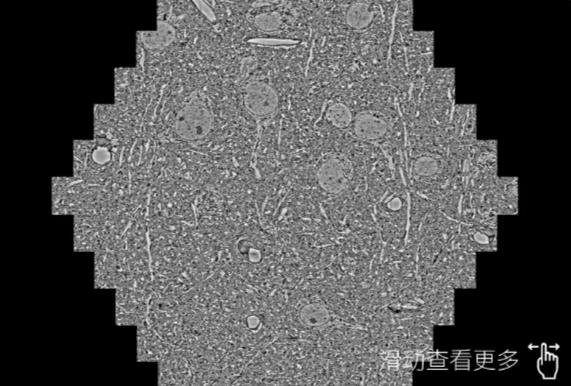

鼠脑切片。左图使用百色蔡司百色扫描电镜MultiSEM706对165μmx143pm面积区域成像,耗时仅需1.5秒。右图为鼠脑切片中30μm区域放大效果。样品由芝加哥大学B.Kasthuri提供。